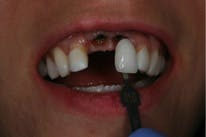

As previously stated, the gingival flap performed on the patient during the implant surgery resulted in blunted papillae on all four of the maxillary incisors, revealing one millimeter of cementum on the lateral incisors and shrinking the tissue making the healing abutments visible over the flipper. Composite was added to the apical portion of the flipper to mimic tooth structure and conceal the abutments (refer to figure 5).

The patient and oral surgeon agreed to do a cosmetic procedure called a subepithelial connective tissue graft to correct the problem. The subepithelial connective tissue graft produces exceptional color matching at the recipient site and should be considered whenever soft tissue grafting is recommended in an area of esthetic concern (Sclar, 2003). This patient received a closed bilateral palatal subepithelial connective tissue graft one month after the implants were placed. The procedure went as followed: A horizontal incision was made on the palate approximately three millimeters apical to the premolars and ranged from the mesial of the first premolar to the distal of the second premolar. A second incision was then made, which determined the thickness of the donor site. The tip of the scalpel was then reinserted inside the second incision, parallel to the palatal tissue and another incision was made, which created a subepithelial pouch. Following, vertical incisions were made within the pouch through the connective tissue to define the width of the donor site. An incision was made at the most apical portion and the connective tissue was then dissected from the subepithelial pouch. Donor tissue is composed of connective tissue, epithelium, fat, and periosteum. It was instantaneously taken and placed over the recipient bed, where it was then adjusted and sutured into place. The recipient site was prepared beforehand by revealing some connective tissue and obtaining a blood supply for the donor tissue. An absorbable collagen dressing (CollaPlug) was then placed in the subepithelial pouch to fill the dead space and aid in hemostasis. The wound was then sutured closed and healed by secondary intention (Sclar, 2003).